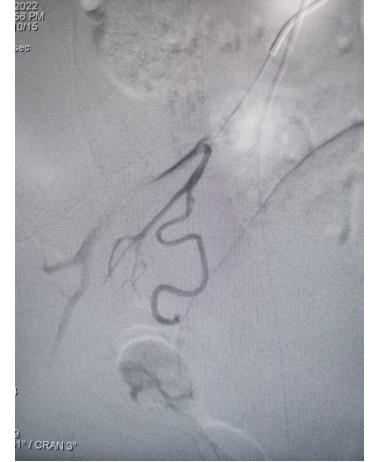

51歲的郭女士,因反復(fù)胸痛3天,加重2小時(shí)入院,入院后胸痛癥狀反復(fù)發(fā)作,檢查心電圖提示前壁導(dǎo)聯(lián)ST段明顯壓低,在此危急時(shí)刻心九科值班醫(yī)生陶醫(yī)生立即啟動(dòng)導(dǎo)管室,心九科介入團(tuán)隊(duì)行冠脈造影提示患者前降支近段99%狹窄,患者病情危在旦夕,遂立即行支架植入術(shù)解除冠脈狹窄,患者生命得以及時(shí)救治。

冠脈手術(shù)前

冠脈手術(shù)后